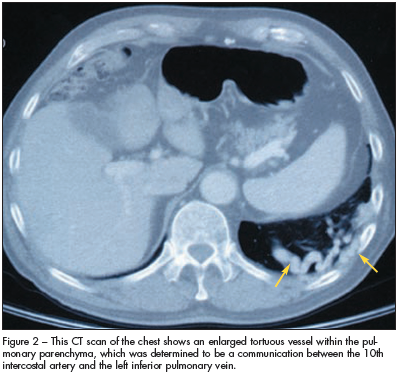

A CT scan of the chest reveals an enlarged tortuous vessel within the pulmonary parenchyma (Figure 2). This vascular structure is interpreted as a communication between the 10th intercostal artery and the left inferior pulmonary vein. A pulmonary angiogram demonstrates no communication between a pulmonary artery and a pulmonary vein. A systemic to pulmonary arteriovenous fistula is diagnosed.